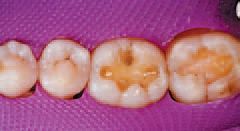

After inspecting the old amalgam restorations (Fig. 2), a rubber dam was then placed (Fig. 3). Next, using Sybron Dental’s Axis course diamond bur, KS3, the amalgam restorations and all damaged tooth structure were removed (Fig. 4).

All remaining sharp edges of the preparation were then beveled with Sybron Dental’s Axis fine finishing diamond #846-016, completing the preparations (Fig. 5). Ivoclar Vivadent’s AdheSE® One F self-etch dental adhesive was applied to tooth No. 30 using the VivaPen™ delivery system (Fig. 6), leaving a shiny bonded surface (Fig. 7).